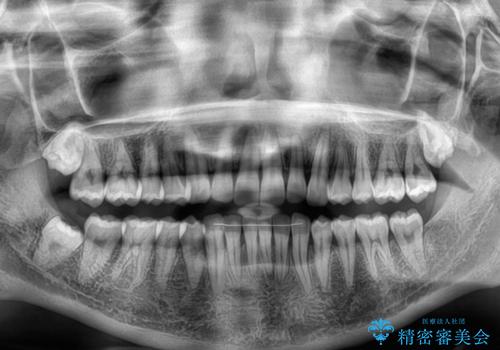

マウスピース矯正特有の、奥歯が噛みにくくなるという現象の解消に少し期間をいただきましたが、日々の装着時間を遵守していただき、綺麗な歯列に整えることができました。